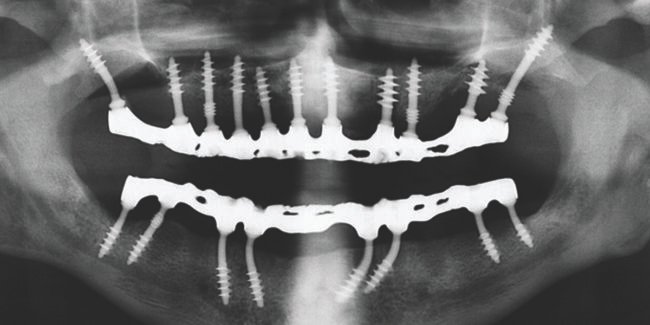

Sciences have always been given importance in India. And in recent years just like other sciences, developments in Basal Implantology are countless. People that choose dentistry as a career has also increased drastically. Numerous institutes offer Dental Implant Courses and provide practical Dental Implant Training in India one of the most recognizable names in this…